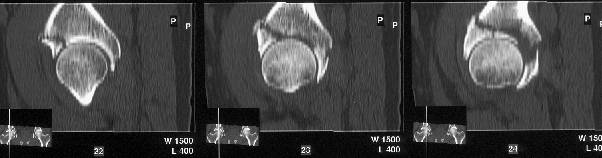

The iliac oblique reveals a displaced fracture of the posterior column, and it appears that the femoral head is not congruous with the acetabulum.

AP, obturator oblique films and a CT scan will better reveal the extent of the injury.

The CT scan confirms what the iliac oblique showed - the acetabulum is incongruous, and the femoral head is following the caudal piece medially. The other thing the femoral head is doing is grinding up against that displaced fracture. This is going to lead to erosion of the femoral head cartilage, and rapid onset of post-traumatic arthritis.

Yes it does. The CT scan reveals a fracture through the weight bearing dome.